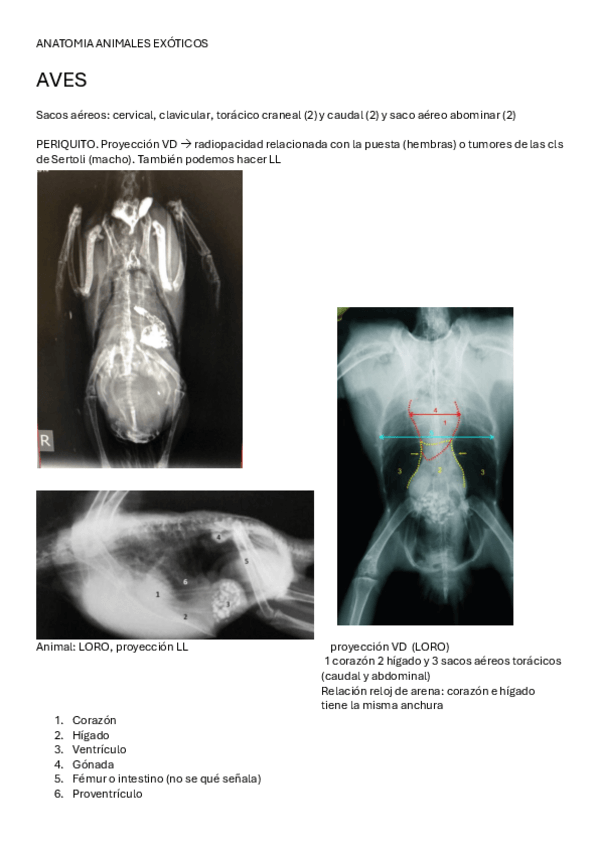

He publicado nuevos apuntes de 3º Diagnóstico Por Imagen: resumen-anatomia-exoticos.pdf

He publicado nuevos apuntes de 3º Diagnóstico Por Imagen: 29.-Anatomia-de-los-animales-exoticos.pdf